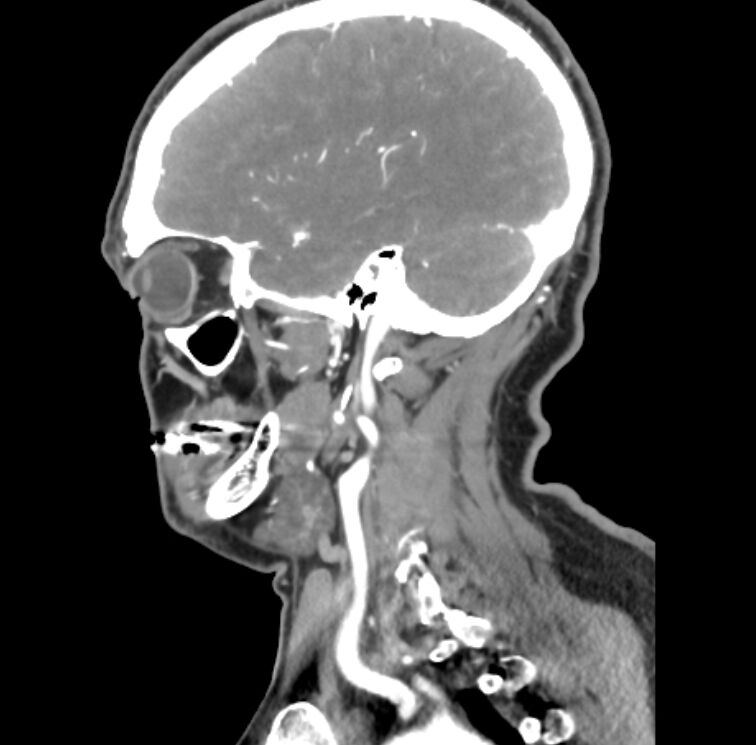

29.80歲男性抽菸且合併高血壓、糖尿病病史,接受頸動脈血管攝影檢查之結果如附圖。則下列敘述何者錯誤?

(A)診斷為外頸動脈(external carotid artery)狹窄

C是ICA支配的ophthalmic artery、D也只會在ICA成立。

順便記得一件事情吧,慣例是anterior放左邊這樣,所以後面(右邊)的就是ICA